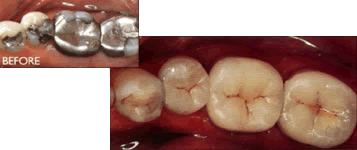

For years there has been debate in the dental profession regarding the pros and cons of using silver amalgam fillings, which contain about 50% mercury, to restore cavities. While it has not been proven scientifically mercury can harm you, we have chosen to not use silver amalgam/mercury fillings, as the technology involved with them is well over 100 years old. There are also several drawbacks to them, which can cause trouble for teeth with silver fillings.

At our office we prefer to provide our patients with the newest and best alternatives available, which are bonded ceramic composite resins. Not only do they look natural, they provide a much better service and protection for your teeth, as they eliminate all the shortcomings of the old fashioned silver fillings. They seal the teeth better, insulate against hot and cold better, and if they wear down they can be Amalgams/Mercury Silver Fillings repaired more easily. Many people who are undergoing a cosmetic improvement on their front teeth elect to have dark silver fillings in their back teeth replaced with the bonded ceramic resins to provide a total cosmetic improvement. Please call the office if you want to look into replacing any of your old, unsightly silver fillings.